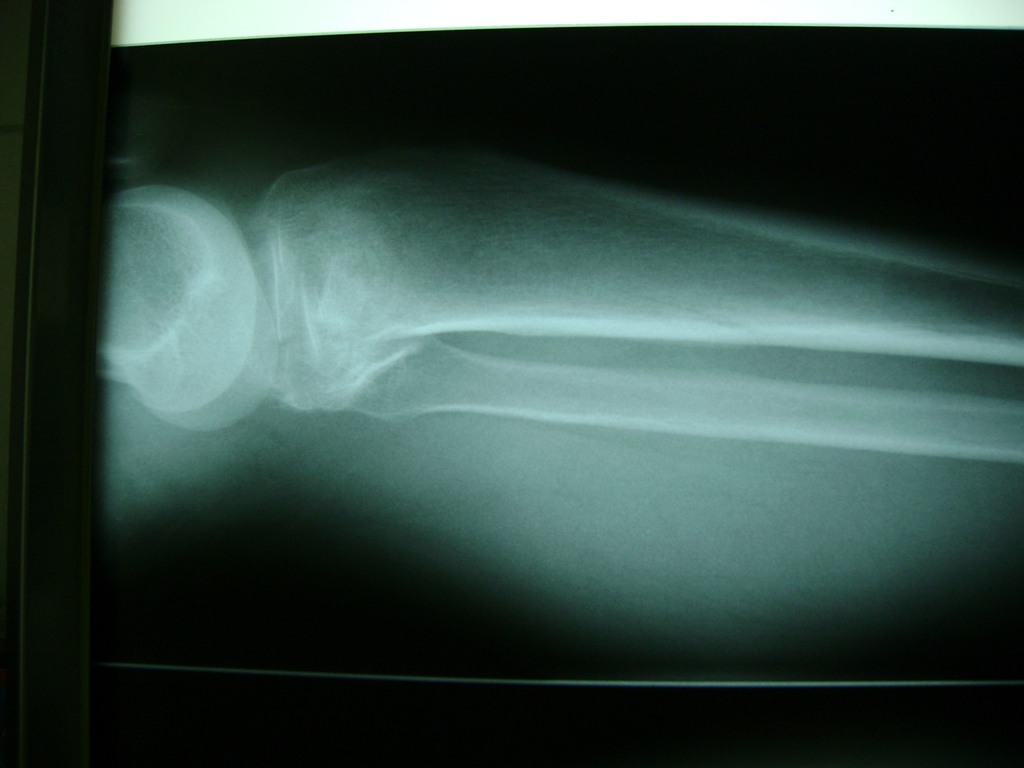

Cirugías de Tobillos